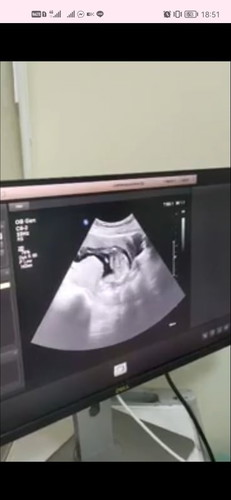

15 วีค หมอบอกว่าท่านอนพิสดารมากหัวอยู่ล่างเท้าอยู่บน แม่บ้านไหนเป็นบ้างค่ะ หรือเป็นแต่เราคนเดียว อยากรู้ว่าปกติหรือผิดปติค่ะ

เปนเหมือนกันเลยค่ะ15วีค4วัน ไปซาวมาเมื่อวาน หัวยุ่ล่างเท้ายุ่บนนอนเกาหัวสบายเลย